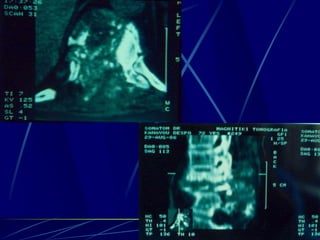

T.B.C.

Φυματίωση της σπονδυλικής στήλης